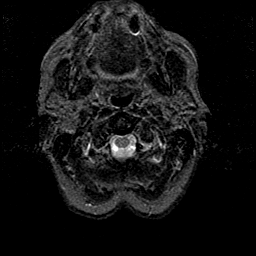

Alzheimer's disease MR T2-weighted -- Slice #0

[Home][Help][Clinical][Tour 1][Tour 2] Slice 0